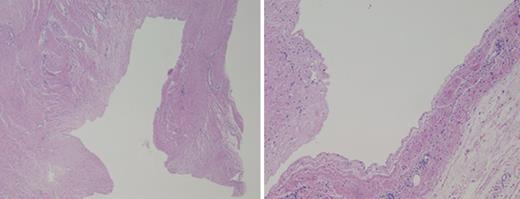

Intraoperatively, the aspirated cystic fluid was clear and devoid of malignant cells. Histologic analysis of the unilocular cyst revealed a primarily fibrous wall with some adipose tissue and associated vasculature. The cyst lacked a true epithelial lining and any malignant features such as hypercellularity, hyperchromasia, cellular pleomorphism or increased mitoses (Fig. 3). The final pathologic diagnosis was that of a benign, fibrous-walled cyst.

Histology of the cyst shows the lack of a true epithelial lining. No malignant features are visualized.